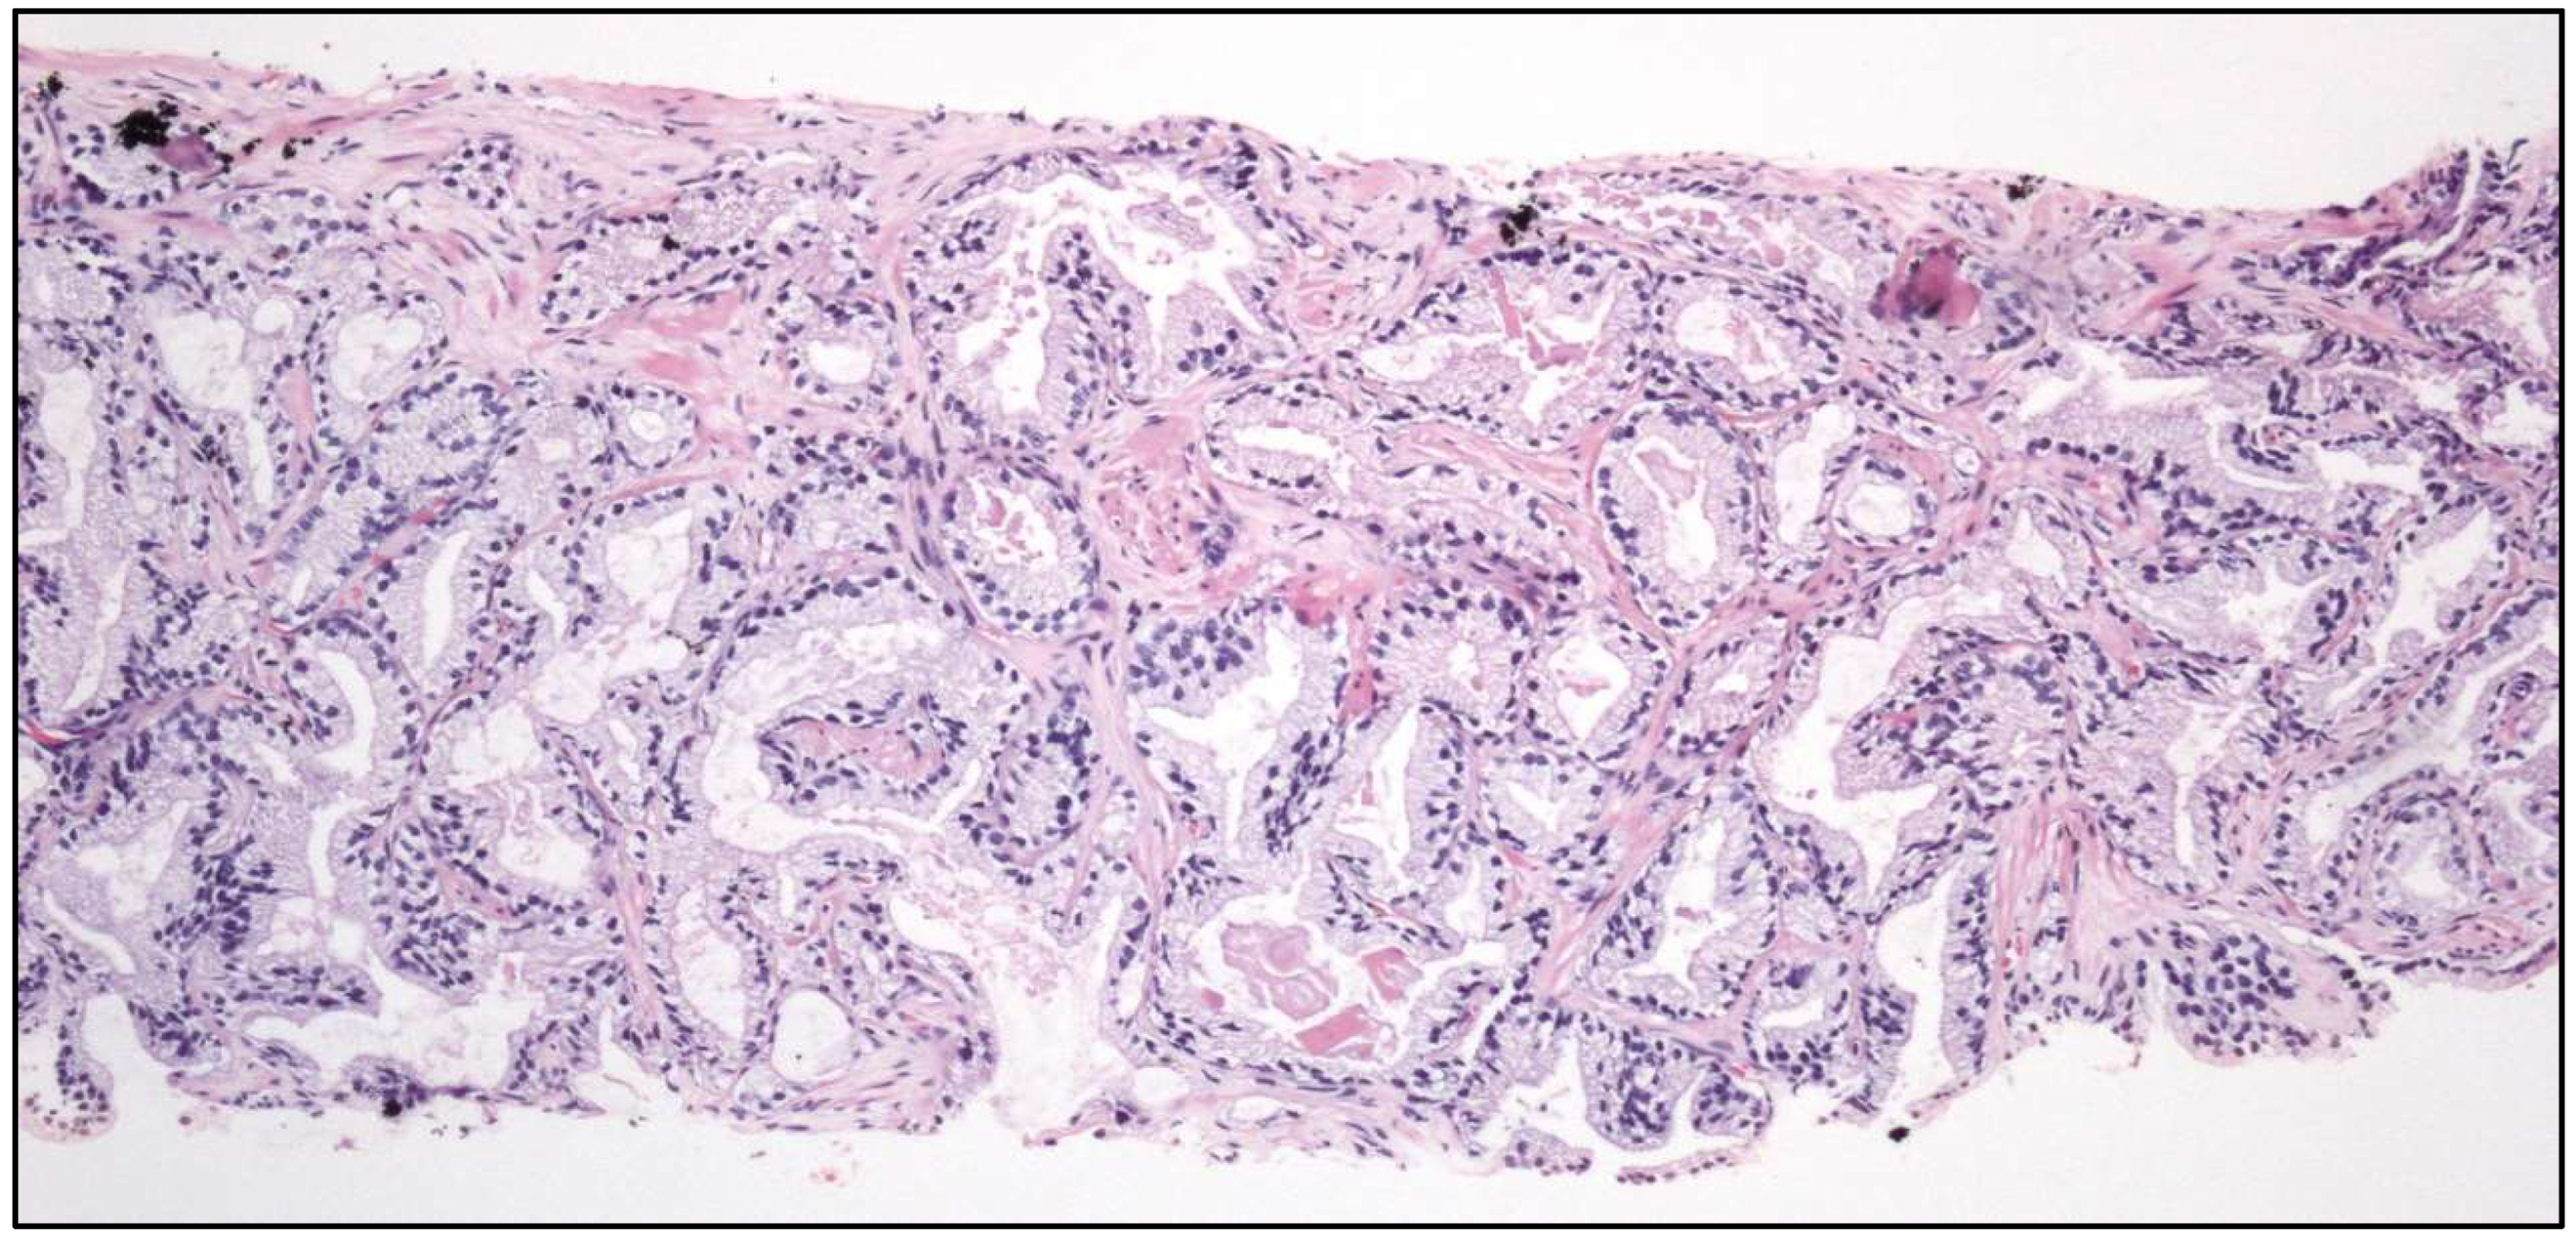

- Well-differentiated papillary mesothelial tumor (Figure 4).